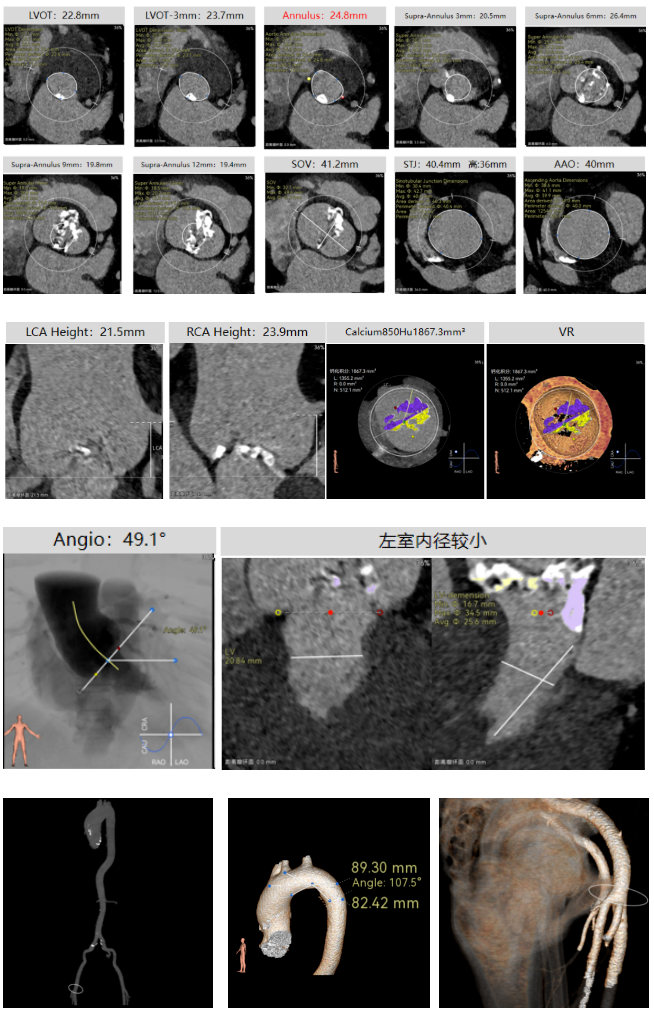

彭小平教授 南昌大学第一附属医院 不断探索医疗可能,筑牢患者长期保障 TAVR 治疗的终极目标,不仅是完成一次手术,更是为患者构建长期稳定的生命保障,而瓣膜耐久性是直接关乎患者后期是否需要二次手术的关键所在。全球首款预装干瓣的问世,为临床提供了全新的选择方案。厂家的15 年质保承诺,是源于材料研发的突破与临床验证的底气。从临床角度,如未来瓣膜可以耐久15年,则可大大减少患者反复就医的身心负担与经济压力,本质上是为患者的长期健康 “投保”。 人生的每一次选择,都需要慎重。相信在行业的前行中,我们不断探索医疗的可能性,让每一次治疗都能真正护航患者长远健康! 患者病史 主诉与现病史:3 年前开始出现胸闷、气促,活动后(如上楼、上坡)症状加重,休息后可缓解,当地医院心脏彩超提示主动脉瓣狭窄,未予特殊治疗;2 年前发现血压轻度升高,口服阿奇沙坦片(40mg,每日 1 次)降压,血压控制尚可;近 1 个月胸闷气促症状明显加重,2025 年 10 月 13 日外院心脏彩超提示主动脉瓣重度狭窄,为进一步诊治入院。 既往史:高血压病史 2 年,规律服用阿奇沙坦片(40mg qd);1 年余前因外伤致腰椎骨折,保守治疗后痊愈;有慢性阻塞性肺疾病病史;有胃窦糜烂、十二指肠球部溃疡史,2023 年曾发生急性上消化道出血;有真菌性食管炎、多发性结肠息肉病史。 术前超声提示:主动脉瓣钙化,主动脉瓣狭窄(重度),左室肥厚,升主动脉增宽。 二尖瓣反流(轻度),三尖瓣反流(轻度),肺动脉瓣高压(轻度)。 左室舒张功能减低,收缩功能正常,左室射血分数 74.7%。 术前CT:Type0型二叶瓣,瓣叶增厚并极重度钙化,钙化主要分布在瓣叶基底部,延伸到左室流出道。主动脉瓣环径24.8mm;升主动脉狭窄后扩张至主动脉弓,双侧瓣叶开口高度可,窦部空间可,STJ内径增宽,升主动脉内径可,预估冠脉低风险;主动脉水平夹角49.1°,非横位心;主动脉弓角、弓距可;“自杀左室”,建议术前补液,ECMO湿备,术中注意循环崩溃。 外周双侧入路内径可,髂总动脉有零星散状钙化,双侧股动脉均能通过20F大鞘,右股低分叉。 手术策略:推荐使用右侧股动脉为主入路,左侧股动脉为辅助入路;右股分叉上方1cm穿刺;推荐使用18mm球囊预扩,预装AV23瓣膜。 手术过程:在右股动脉穿刺建立通路后,顺利送入大鞘,经食道超声及血管造影确认路径稳定。18mm球囊预扩后评估冠脉灌注良好,后将Prostyle A® AV23瓣膜精准释放于目标位置,20mm球囊后扩,超声显示轻微瓣周漏,术后即刻造影显示无明显反流,峰值压差由术前的80mmHg降至12mmHg,心功能明显改善,患者生命体征平稳。 18球囊预扩无腰无漏 输送器跨瓣顺利 定位 平稳释放瓣膜 20球囊后扩 最终造影,位置良好,轻微瓣周漏 Prostyle A®预装干瓣——助力临床最优化解决方案 1、流入端桶状设计:流入端桶状的设计,锚定迅速,有效减少释放步骤,提升植入稳定性; 2、平衡的收腰设计:二叶瓣小心室患者对瓣膜径向支撑力提出更高要求,Prostyle A®均衡的收腰设计可更好适应小瓣环及不规则瓣口结构,保证了EOA,有效降低了循环崩溃风险,提高瓣膜的耐久性; 3、预装干瓣 便捷顺安:金仕生物专利抗钙化技术运用纳米技术去除组织内的细胞碎片和磷脂,封闭游离醛基,从根本上阻断了瓣膜钙化的多项因素,显著提升了瓣膜的耐久性;同时,相比较传统戊二醛保存方式,干式存储最大限度的保留心包的亲水亲油平衡,还原组织天然曲柔性,进一步保障了瓣叶开合,保证长期耐久性; 专家简介 彭小平 南昌大学第一附属医院(点击查看专家详细简历) · END ·